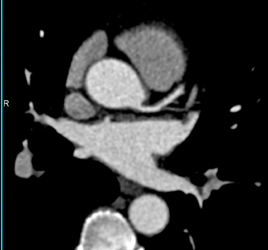

Left Main Arises Off Right Coronary Artery